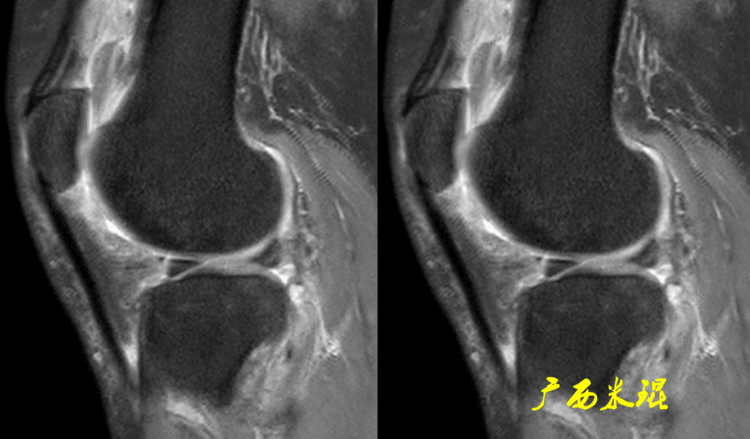

下面矢状位MR是外侧半月板后角部分切除手术后,片上我们发现半月板后角部分缺失,半月板信号正常(因为手术前半月板没有退变)。

下面矢状位MR是内侧半月板后角水平撕裂部分切除手术后,半月板后角部分缺失,信号仍然不正常(因为手术前半月板已经有退变),真正的情况是关节镜下半月板外观是正常的,MR上看见的高信号影是半月板退变的Ⅱ级信号所致,由于手术切除面达退变的层面,MR上容易误诊为Ⅲ级信号。

下面矢状位MR是内侧半月板后角纵形撕裂缝合手术后,半月板外观完整,无分离,缝合处小片状稍高信号,这个高信号几乎不可能消失(半月板损伤痕迹永远存在)。

内侧半月板后角纵形撕裂缝合手术后,半月板外观完整,无分离,缝合处的线状稍高信号一般情况下也永久存在。

如同下面这张MR,左侧图像为手术前的,右侧图像为手术后的,术后病人疼痛等症状仍然存在,复查MR见外侧半月板前角分层,半月板前角的处理是有一定难度的,有经验的医生会考虑可能是手术者对前角的处理不够熟悉,没有通过另外的办法处理半月板前角的水平裂,不过也只能是猜测而已。所以,对于半月板术后的评估,症状的消失比MR重要!